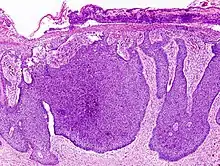

![]() | Basal cell carcinoma | Surgical excision biopsy specimen showing histopathology of basal cell carcinoma. | Category: Histopathology of basal cell carcinoma | Basal cell carcinoma |